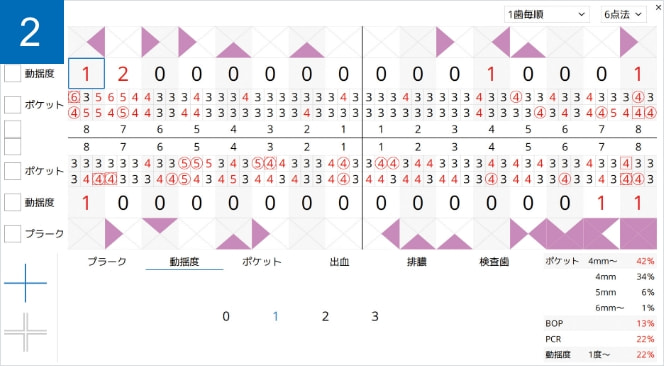

MyGate オプション機能「 X perio(クロスペリオ) 」

歯周病検査の記録やプレゼンテーションを行う事ができる追加可能なオプション機能です。提供文書の印刷までのフローを、スムーズかつ効果的に行えます。

デンタルチャート作成

歯牙の種類や病状、補綴物などの口腔内の情報を登録する事ができます。

カリエスや補綴物は、近心遠心、唇側(頬側)、舌側(口蓋側)の指定も可能です。

患者説明

検査結果をわかりやすいイラストで表示。

今回・前回・前々回の統計情報とレーダーチャートで経過を確認でき、患者さんのモチベーションの向上・維持に役立ちます。タッチペンで自由に説明を描き込むことができ、説明した内容をそのままMyGateで保存/閲覧することができます。